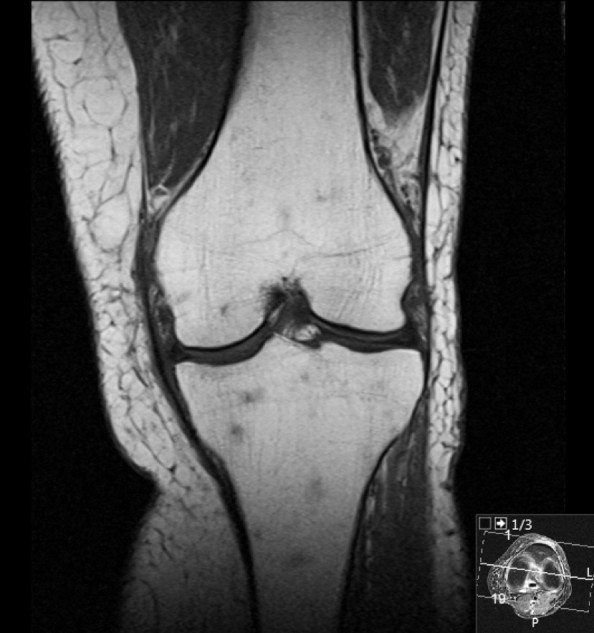

MR-bildet av venstre kne viser flekkvise forandringer med lavt T1-signal i benmargen.

En tidligere frisk kvinne i 70-årene kom til MR-undersøkelse av venstre kne på grunn av et halvt år med smerter i kneet, spesielt ved kneling og trappegang. MR-undersøkelsen viste en degenerativ meniskruptur, som sannsynligvis kunne forklare pasientens symptomer. I tillegg var det flekkvise forandringer i benmargen.

Små signalvariasjoner i benmargen er ikke et uvanlig funn, men i dette tilfellet var funnet mer uttalt enn normalt. Funnet var også til stede på øvrige MR-sekvenser og ga mistanke om at det kunne foreligge sykdom med affeksjon av benmargen. Pasienten ble henvist til fastlegen for videre utredning. CT-undersøkelse av brystkassen, buken og bekkenet med intravenøst kontrastmiddel viste forstørrede lymfeknuter i mesenteriet og leverhilum samt lett forstørret milt.